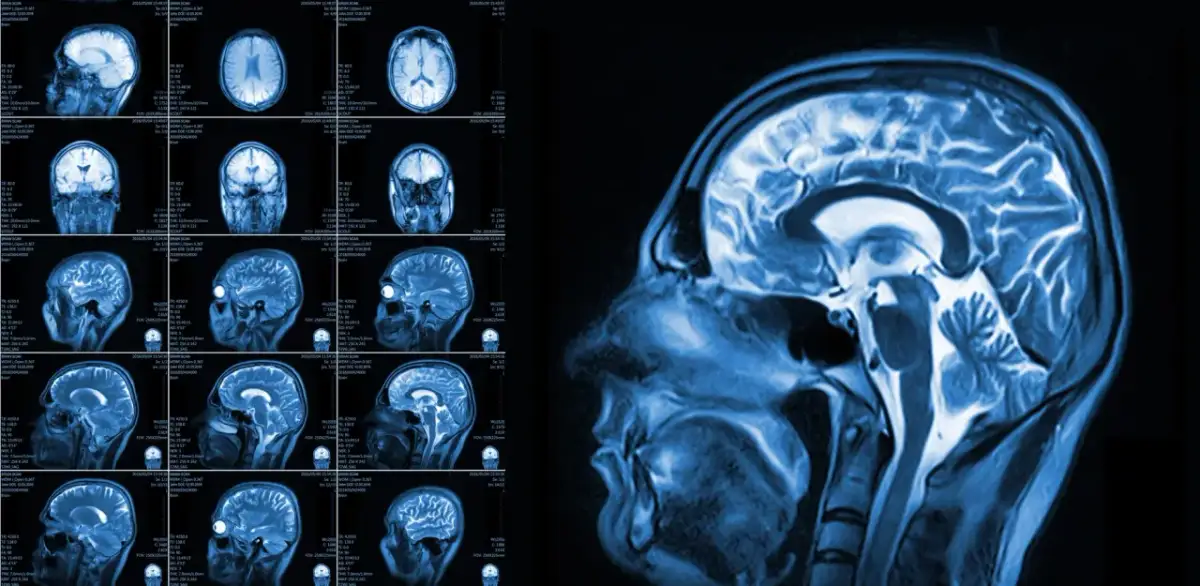

Niewidzialne blizny: Jak depresja fizycznie zmienia strukturę mózgu?Depresja to nie tylko stan emocjonalny, ale choroba, która pozostawia mierzalne ślady w naszym mózgu. Badania neuroobrazowe pokazują, że podczas epizodów depresyjnych dochodzi do zmniejszenia objętości hipokampu, obszaru kluczowego dla procesów pamięci i uczenia się. Podobnie, kora przedczołowa, odpowiedzialna za funkcje wykonawcze takie jak planowanie czy podejmowanie decyzji, również może ulec zmniejszeniu. Zmiany te dotykają także ciała migdałowatego, centrum przetwarzania emocji. Długotrwały stres i podwyższony poziom kortyzolu, hormonu stresu, który towarzyszy depresji, mogą prowadzić do zaniku neuronów i osłabienia połączeń synaptycznych, czyli "dróg komunikacyjnych" między komórkami nerwowymi. To właśnie te fizyczne zmiany są przyczyną wielu trudności, z jakimi się zmagamy.